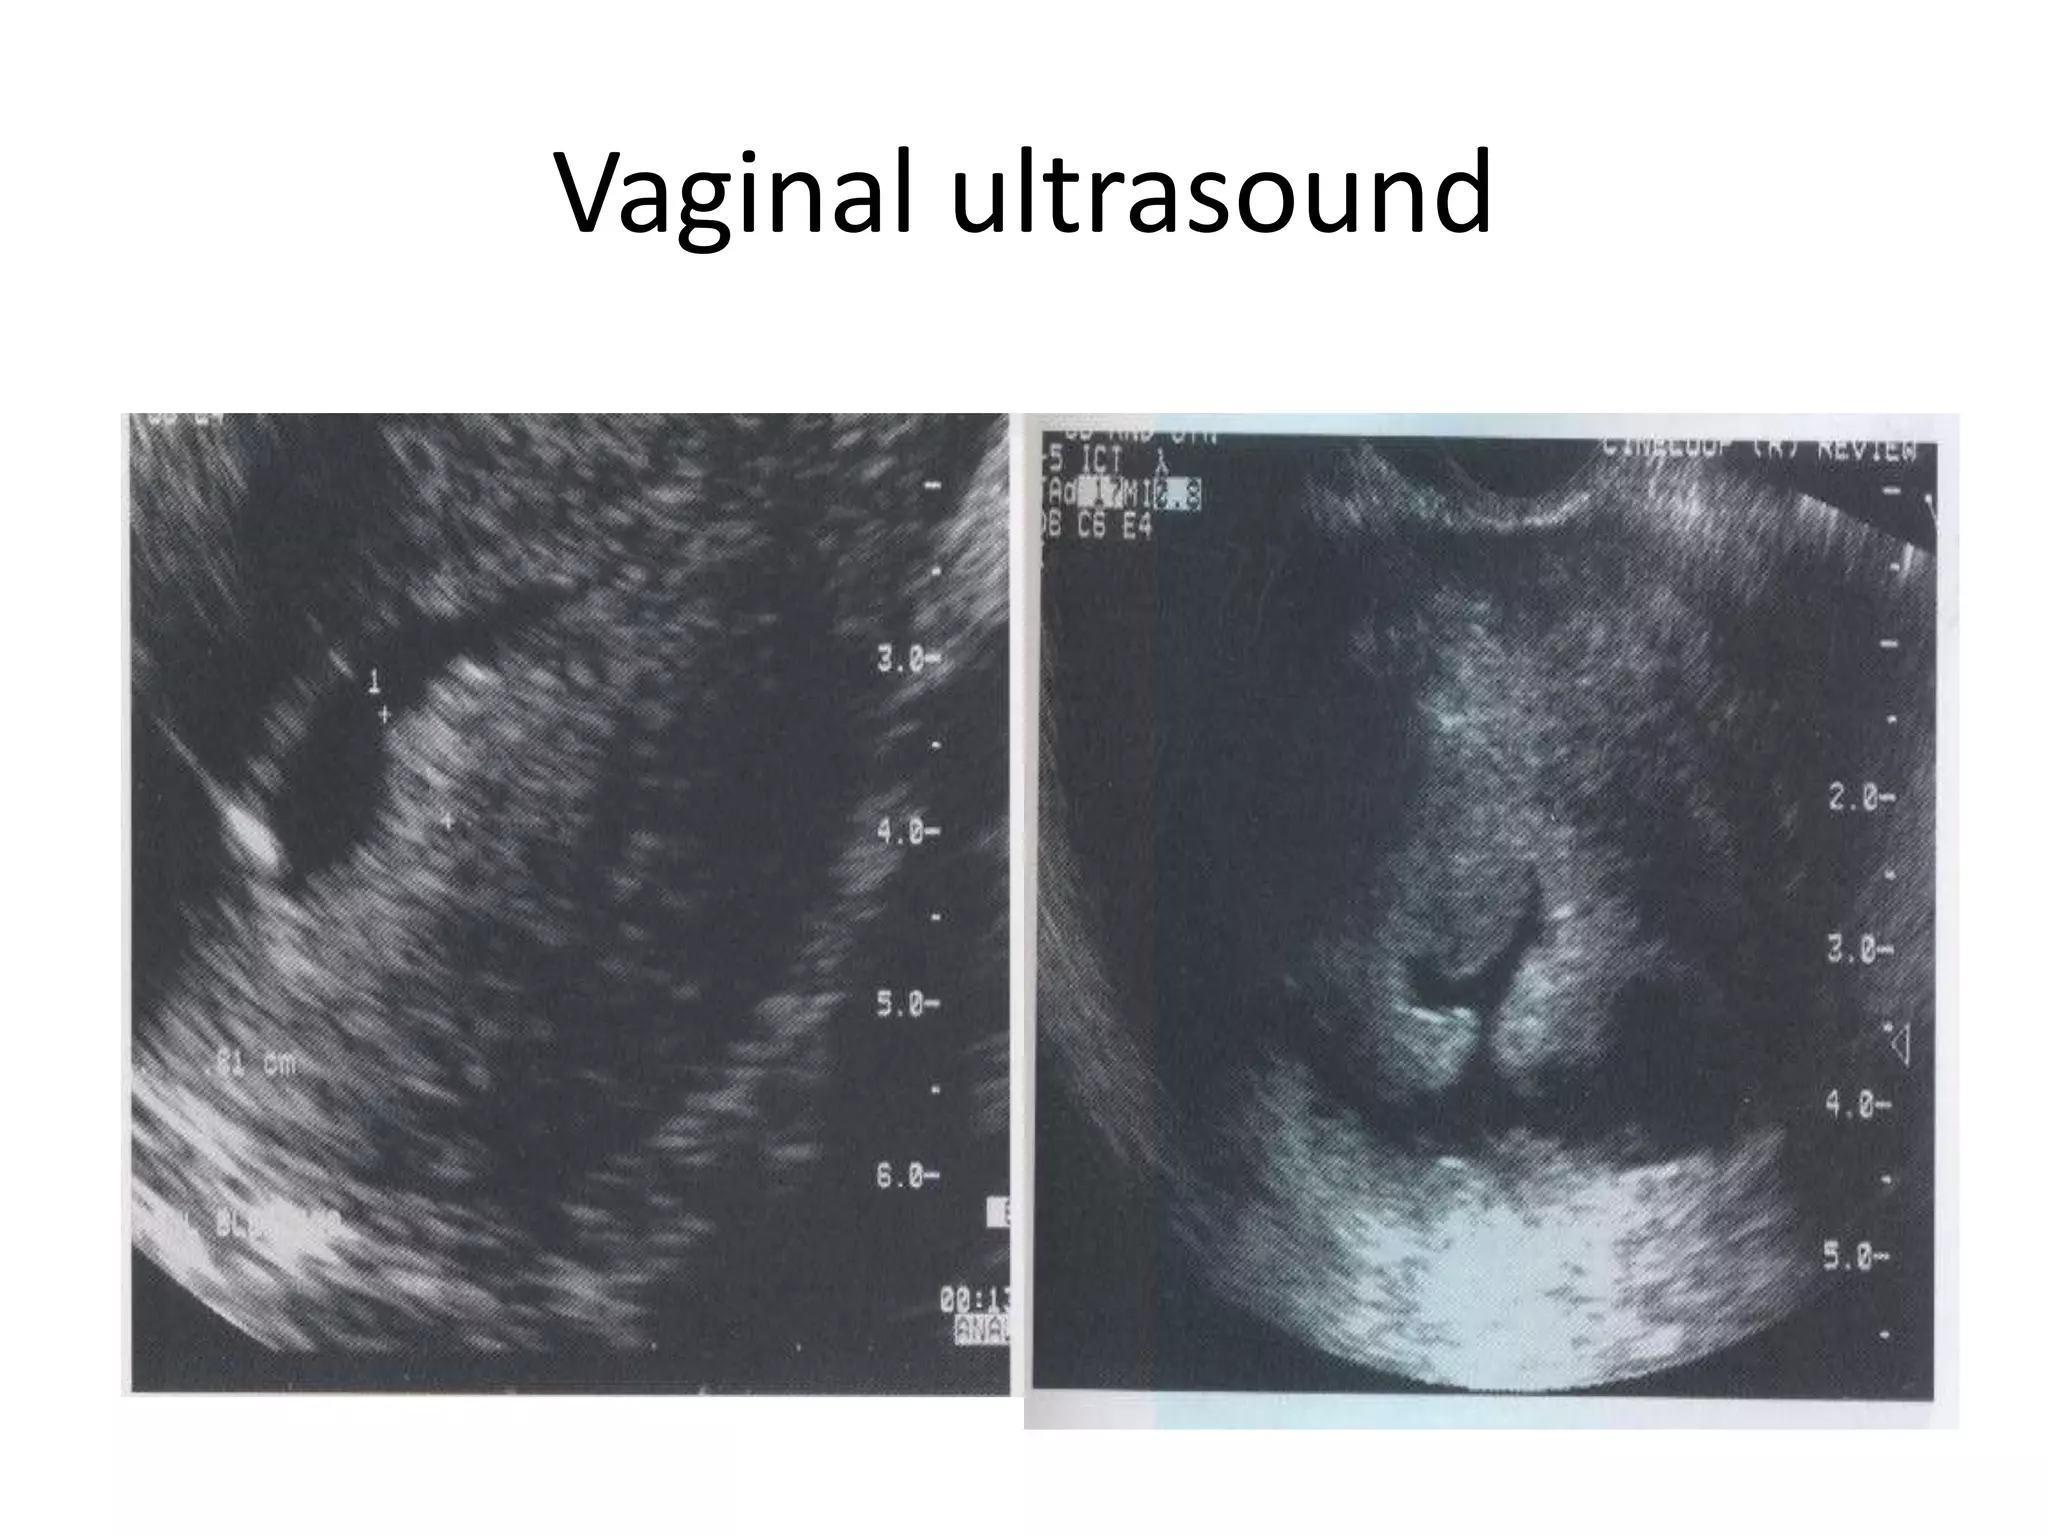

InvestigationsVaginal ultrasound

HysteroscopyVaginal ultrasound

Focal Simple Hyperplasia

Atypical Hyperplasia